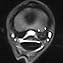

• MRI and its role in distal limb soft tissue diagnosis